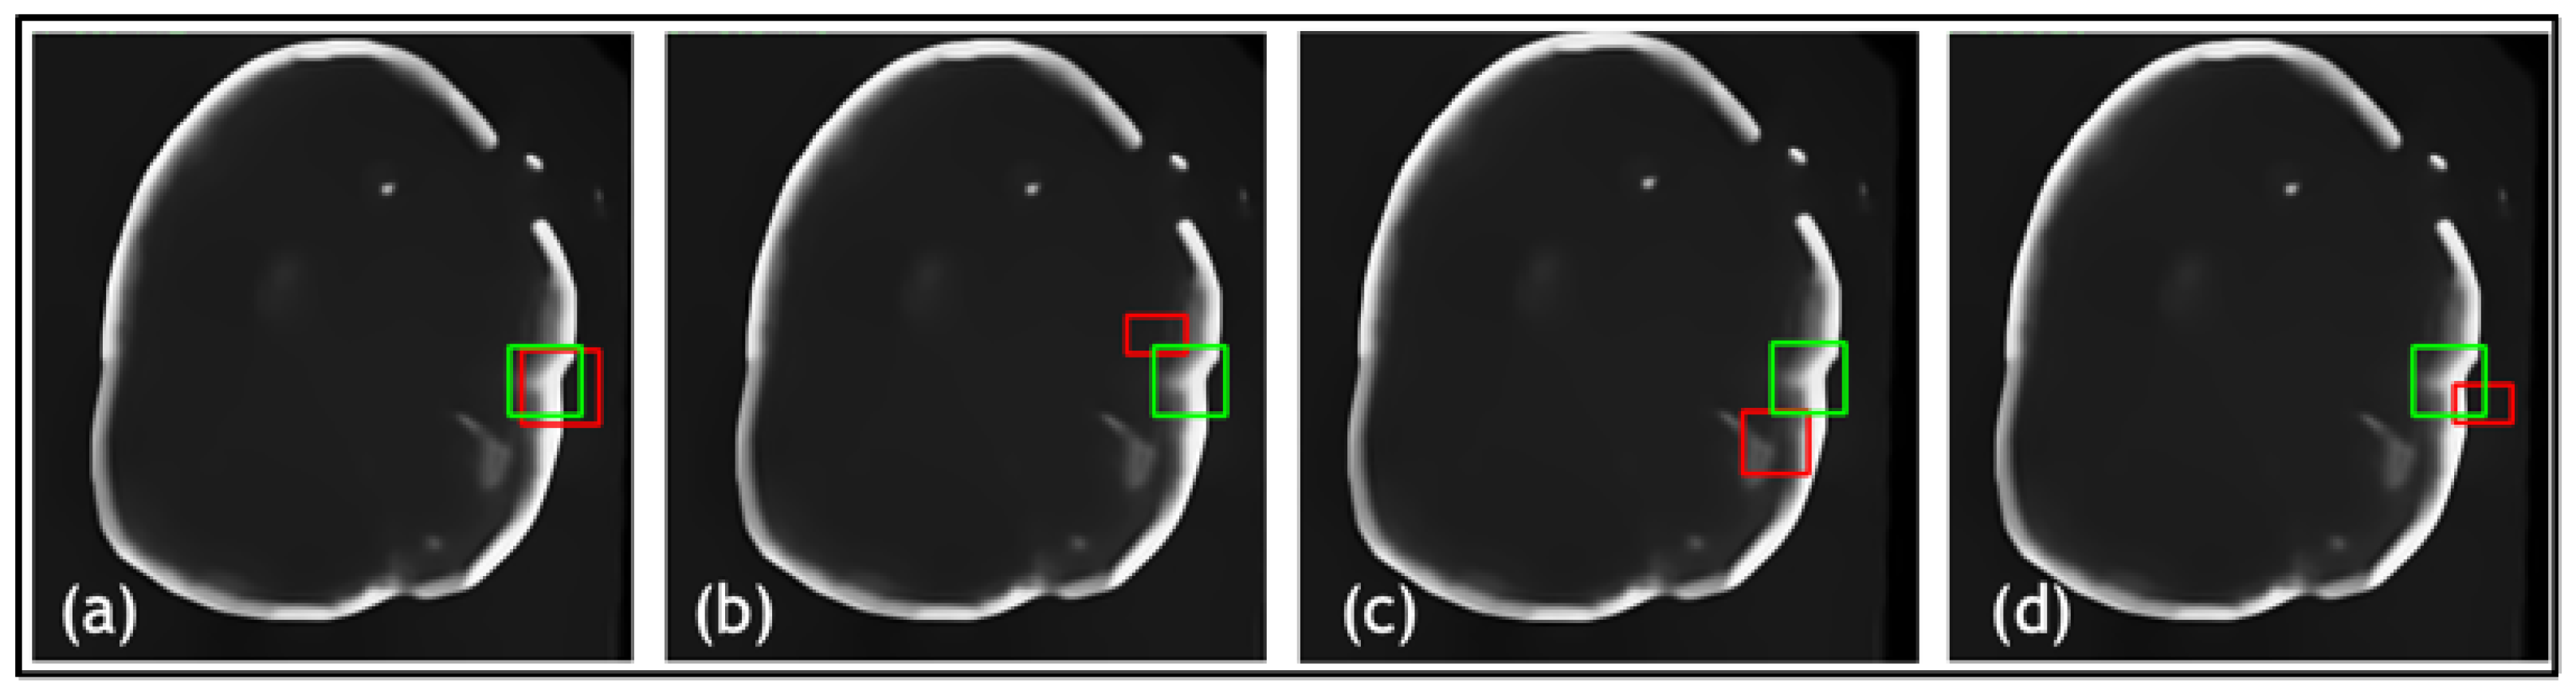

- In TED, the transformer is adapted to take in images and slide across Regions of Interest (ROIs) provided by AGs. This design aims to adaptively deal with different types of noise artifacts and thus effectively detect a variety of anomalies including tooth decay and numerous lesions across two modalities.

- A new loss function is proposed along with TED, which combines a sliding box, Intersection Over Union (IOU), and Mean Squared Error (MSE). It compares the IOU and MSE between the predicted and real bounding boxes to evaluate the regions of focus chosen by the AGs.